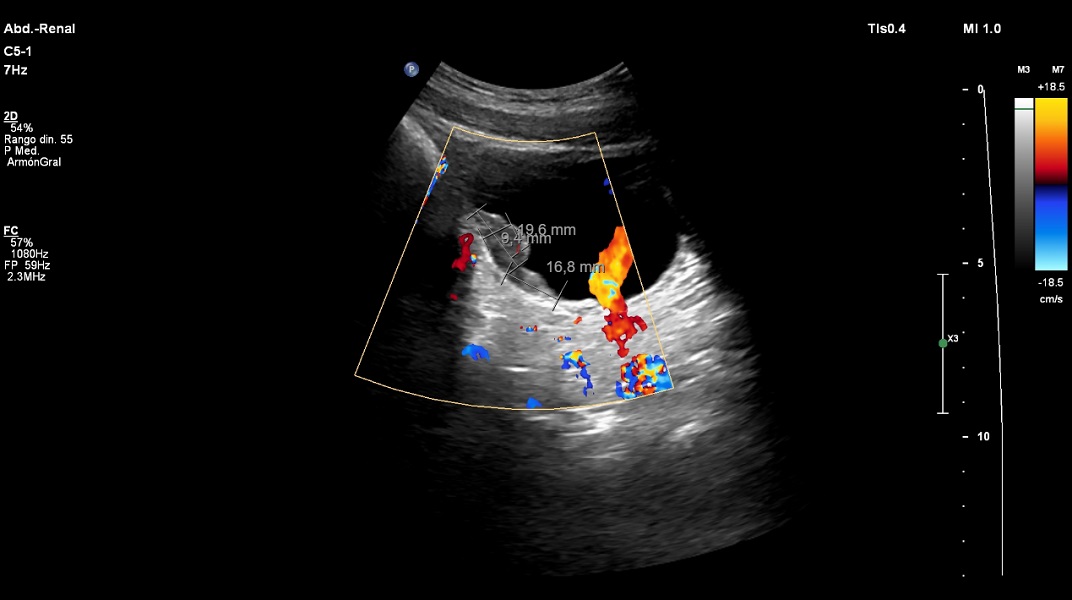

Niño de 12 años procedente de la República de Mali (África occidental) y residente en España desde hace 6 meses, traído a consulta de Atención Primaria por primera vez por varias lesiones inflamatorias en cuero cabelludo y hematuria macroscópica algo dolorosa de larga evolución. No hay otros convivientes afectos. Habla francés, pero no español. No aporta calendario de vacunación. Exploración física: peso 44,3 kg (p38, -0,30 DE); talla: 147 cm (p19, -0,87 DE) (Carrascosa, et al. 2017); tensión arterial (TA): 100/65; frecuencia cardiaca (FC): 81 lpm; temperatura: 35,9 °C. Presenta lesión supurativa en cuero cabelludo en forma de placas alopécicas en varias localizaciones sin arrancamiento del pelo (Figura 1). Pene normal circuncidado, sin lesiones en glande. El resto de la exploración por aparatos es normal. Se realiza estudio analítico de primer nivel del niño migrante sin alteraciones relevantes, salvo presencia de eosinofilia periférica (eosinófilos 2580/µl) sin anemia, recuentos absolutos de inmunoglobulinas en rango normal, perfil férrico y tiroideo sin alteraciones, tiempos de coagulación normales. En el estudio de orina se confirma hematuria macroscópica sin proteinuria, leucocituria ni nitritos y urocultivo negativo a las 48 horas de incubación. Estudio coprológico sin alteraciones. El paciente es remitido a urgencias del hospital de referencia e ingresa en hospitalización para completar estudio. Prueba de Mantoux negativa. Serologías negativas. Cultivo positivo de raspado de cuero cabelludo para Trichophyton violaceum. Gota gruesa y PCR para malaria negativas. Parásitos en heces negativos. Parásitos en orina: visualización directa positiva para Schistosoma haematobium. Ecografía urinaria: riñones y vía excretora urinaria normal. Vejiga moderadamente replecionada, observándose en pared anterior y lateral derecha dos imágenes polipoideas planas de 19,6 mm y 16,8 mm de longitud y de unos 9 mm de grosor, con escasa vascularización, compatibles con esquistosomiasis urinaria crónica (Figura 2). La evolución es la siguiente: en la consulta de Atención Primaria se inicia tratamiento con terbinafina (250 mg cada 24 horas durante 8-12 semanas) para la tiña del cuero cabelludo, y en el hospital, con praziquantel (20 mg/Kg, 2 veces al día, un día). Paralelamente, se realiza la revisión del calendario vacunal en la consulta de Enfermería y control evolutivo en consultas de Atención Primaria con resolución de las lesiones del cuero cabelludo y de la hematuria.

Figura 2. Imagen ecográfica compatible con esquistosomiasis urinaria crónica